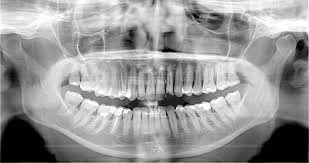

Panoramique dentaire numérique 2D au capteur plan dynamique avec Céphalométrie

Le générateur haute fréquence de 200 kHz assure une émission de radiations efficace et précise et produit des images d'excellente qualité, avec un courant anodique inférieur aux produits de génération précédente. Le résultat : une image plus uniforme dans son noircissement de la région des incisifs et un agrandissement constant des images panoramiques, qui se traduit en une représentation géométriquement plus soignée des structures anatomiques. En plus, le collimateur le plus indiqué est automatiquement sélectionné, sans besoin d'opérations manuelles.

Les facteurs d'exposition et la trajectoire de mouvement s'adaptent facilement à la particularité de chaque patient, grâce à la sélection anatomique, qui inclut le choix adulte/enfant et trois tailles. Le résultat est un compromis optimal entre la dose émise et la qualité de l'image.